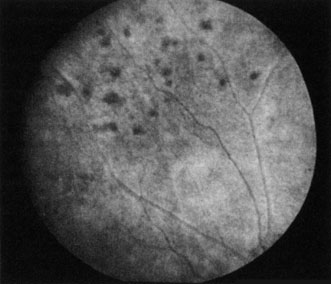

The clinical picture is typically striking. Patients present with a sudden painless loss of vision. The appearance of a cherry-red spot in the fundus is characteristic (Fig. 1).2 The cherry-red spot appears because soon after obstruction of the blood flow to the inner retina, the normally transparent retina becomes opaque and blocks the brownish-red color from the underlying choroid, which is still supplied by blood. Because the retina overlying the foveola is relatively thin, however, the normal color of the choroid is still visible in this area.3,4 Although characteristic, the cherry-red spot is not pathognomonic for central retina artery obstruction.5 Sometimes the characteristic cherry-red spot does not develop; there may be only a slight accentuation of the brownish-red color in the foveola.4 It is not known how long it takes this cherry-red spot to appear, but in a primate model, it has appeared as early as 30 minutes after obstruction.6 An afferent pupil defect is usually present.2

With time, the retinal opacity diminishes, generally leaving an optic nerve that is atrophic (Fig. 1). Frequently, thinned retinal arteries and veins also remain.7,8 No foveolar light reflex is evident, and a finely pigmented appearance of the macula is typical.7 In some cases, arterial collaterals develop at the optic disc.9–11 Rarely, anatomoses that exist between the central retinal artery and the ciliary arteries become visible as preretinal loops (Nettleship collaterals) after an occlusion at the edge of the disc.12,13,378In approximately 20% of patients, an embolus is evident somewhere in the arterial system.14 Emboli are discussed later.

Intravenous fluorescein angiography is useful in showing the details of the abnormal circulation of a central retinal artery obstruction (Fig. 1). The principal abnormality is the delay in the appearance of the dye in the central retinal artery and its branches.2 Rather than the central retinal artery and its branches filling rapidly, considerable time may elapse before the entire arterial system is filled.15 The filling of the retinal arteries is often abnormal, with the fluorescein partially filling an artery (a dye front) or hugging the vessel wall, as in normal venous filling.15

Optic coherence tomography (OCT) of an acute central retinal artery occlusion shows a slight increase in the thickening of the retina and reflectivity of the inner layers of the retina that correspond to the opacity seen clinically (Fig. 1).409 With time, the disc becomes atrophic and the retina thinner.